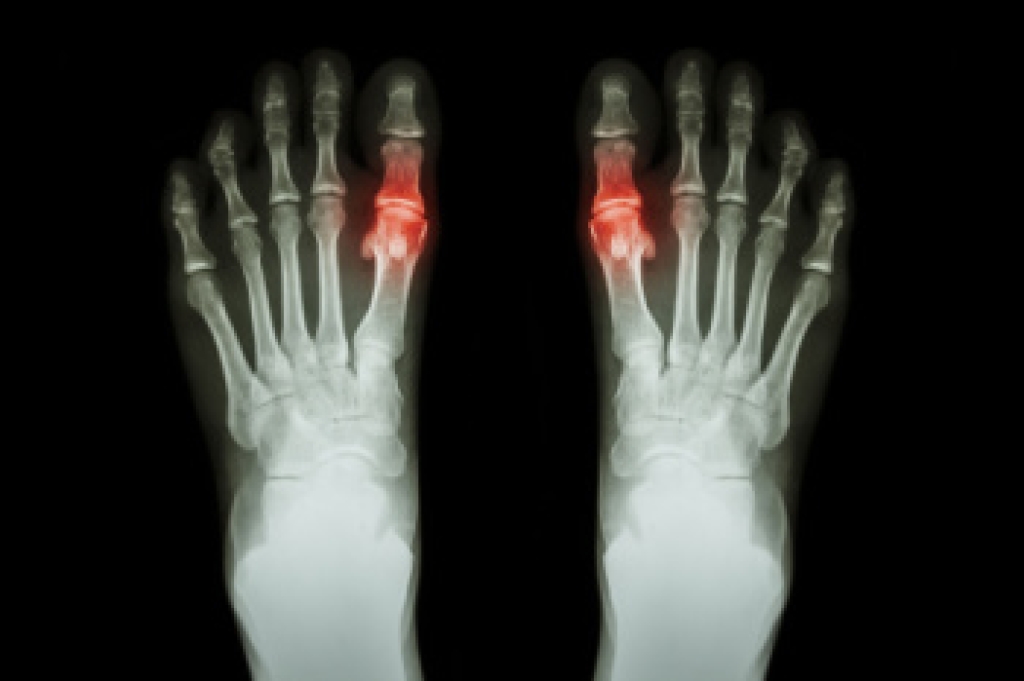

Freiberg’s disease - This can be seen as a deterioration and flattening of a metatarsal bone that exists in the ball of the foot. It typically affects pre-teen and teenage girls, but can affect anyone at any age. Symptoms that can accompany this can be swelling, stiffness, and the patient may limp.